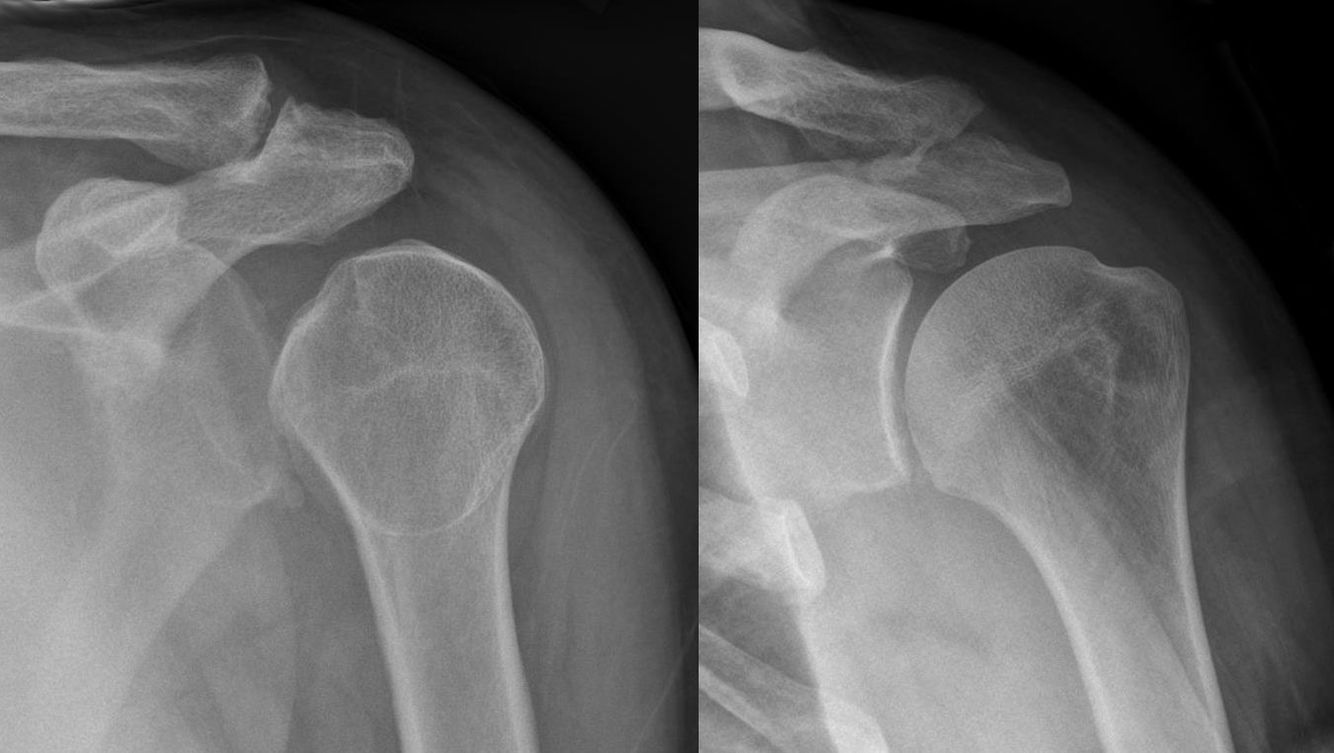

Describe the different types of shoulder dislocations

What is the Lightbulb sign in regards to the shoulder?